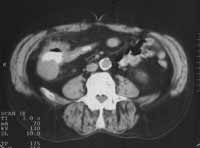

В 10-ти случаях выявлены признаки характерные для рака ободочной кишки: неравномерное утолщение стенок ободочной кишки от 1,0 до 2,6см, нечеткость контуров, повышение плотности окружающей клетчатки, уплотнение переднего листка околопочечной фасции (в случаях рака восходящей и нисходящей кишок) (Рис. 1- 4). В 2-х случаях рак ободочной кишки сопровождался  признаками кишечной непроходимости (Рис. 5). В одном случае массивная опухоль исходила из правой почки и вовлекала восходящую кишку. В другом — выявлена опухоль имеющая неоднородную мягкотканную плотность, относительно четкие контуры расположенная, премущественно экстраорганно по отношению к нисходящей кишке (Рис. 6). В одном случае при пероральном контрастировании ободочной кишки создалось впечатление ракового поражения селезеночного угла толстой кишки, для уточнения исследование повторили после очистительной клизмы и раздувания — в результате выявлен полип на ножке (Рис. 7). При обследовании постоперационных больных — в 1-м случае выявлен околоободочный абсцесс, в другом — явления анастомозита после левосторонней гемиколонэктомии, проявляющегося утолщением стенок кишки в зоне анастомоза до 6мм с выраженным расширением проксимальной части кишки. В двух случаях при КТ исследовании не получено убедительных данных за опухолевое поражение ободочной кишки хотя данные колоноскопии указывали на раковое заболевание или малигнизированный полип.

Рис. 1. Рак печеночного угла толстой кишки: неравномерное утолщение стенки кишки, ее неоднородность, инфильтрация окружающей клетчатки, утолщение близлежащего участка брюшины.